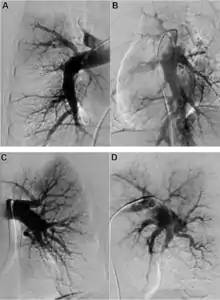

Both V/Q scanning and modern multidetector CT angiography (CTPA) may be accurate methods for the detection of CTEPH, with excellent diagnostic efficacy in expert hands (sensitivity, specificity, and accuracy of 100%, 93.7%, and 96.5% for V/Q and 96.1%, 95.2%, and 95.6% for CTPA).[9] CTPA alone cannot exclude the disease, but may help identify pulmonary artery distension resulting in left main coronary artery compression, pulmonary parenchymal lesions (e.g. as complications from previous pulmonary infarctions), and bleeding from bronchial collateral arteries.[10] Today, the gold standard imaging remains invasive pulmonary angiography (PAG) using native angiograms or a digital subtraction technique.